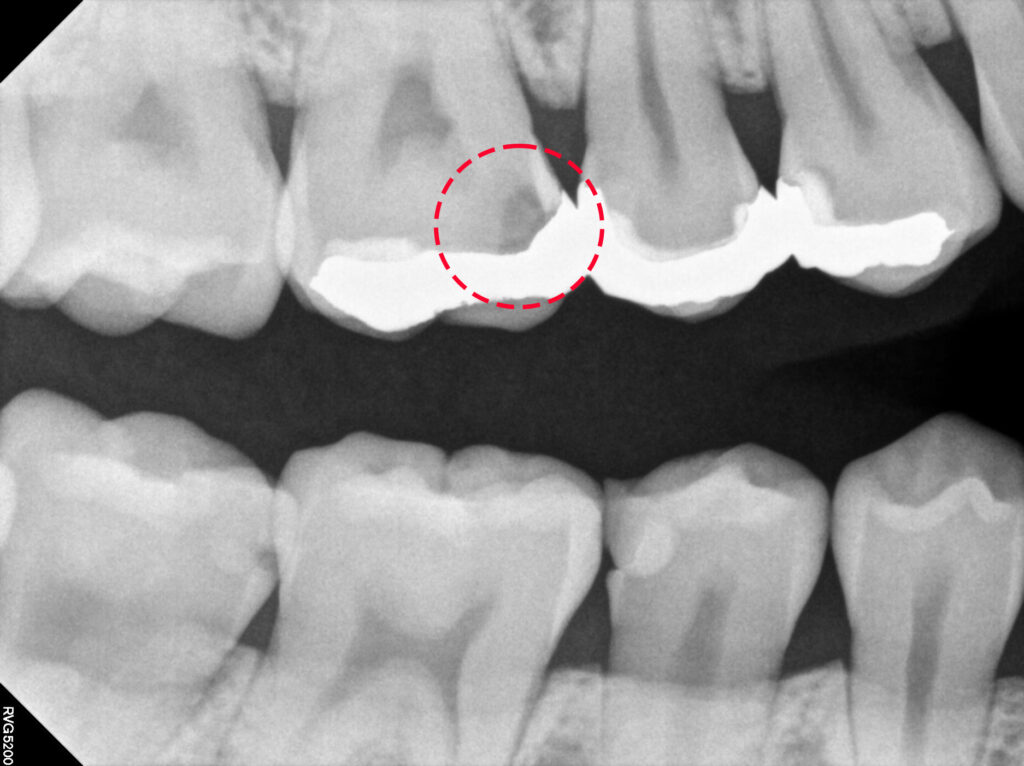

이번 증례는 기존 금 인레이가 수복되어 있던

치아에서 재치료가 필요했던 경우로,

기존 보철물의 변연 적합도가 떨어지거나

2차 우식이 발생한 상황이었습니다.

이에 따라 기존 보철물을 제거하고

내부 상태를 확인한 뒤, 우식 조직을 깨끗하게

제거하는 과정이 선행되었습니다.

이 경우 크라운 치료를 진행하기에는

삭제량이 과도해질 수 있어,

보다 보존적인 접근이 가능한

세라믹 인레이를 선택하였습니다.